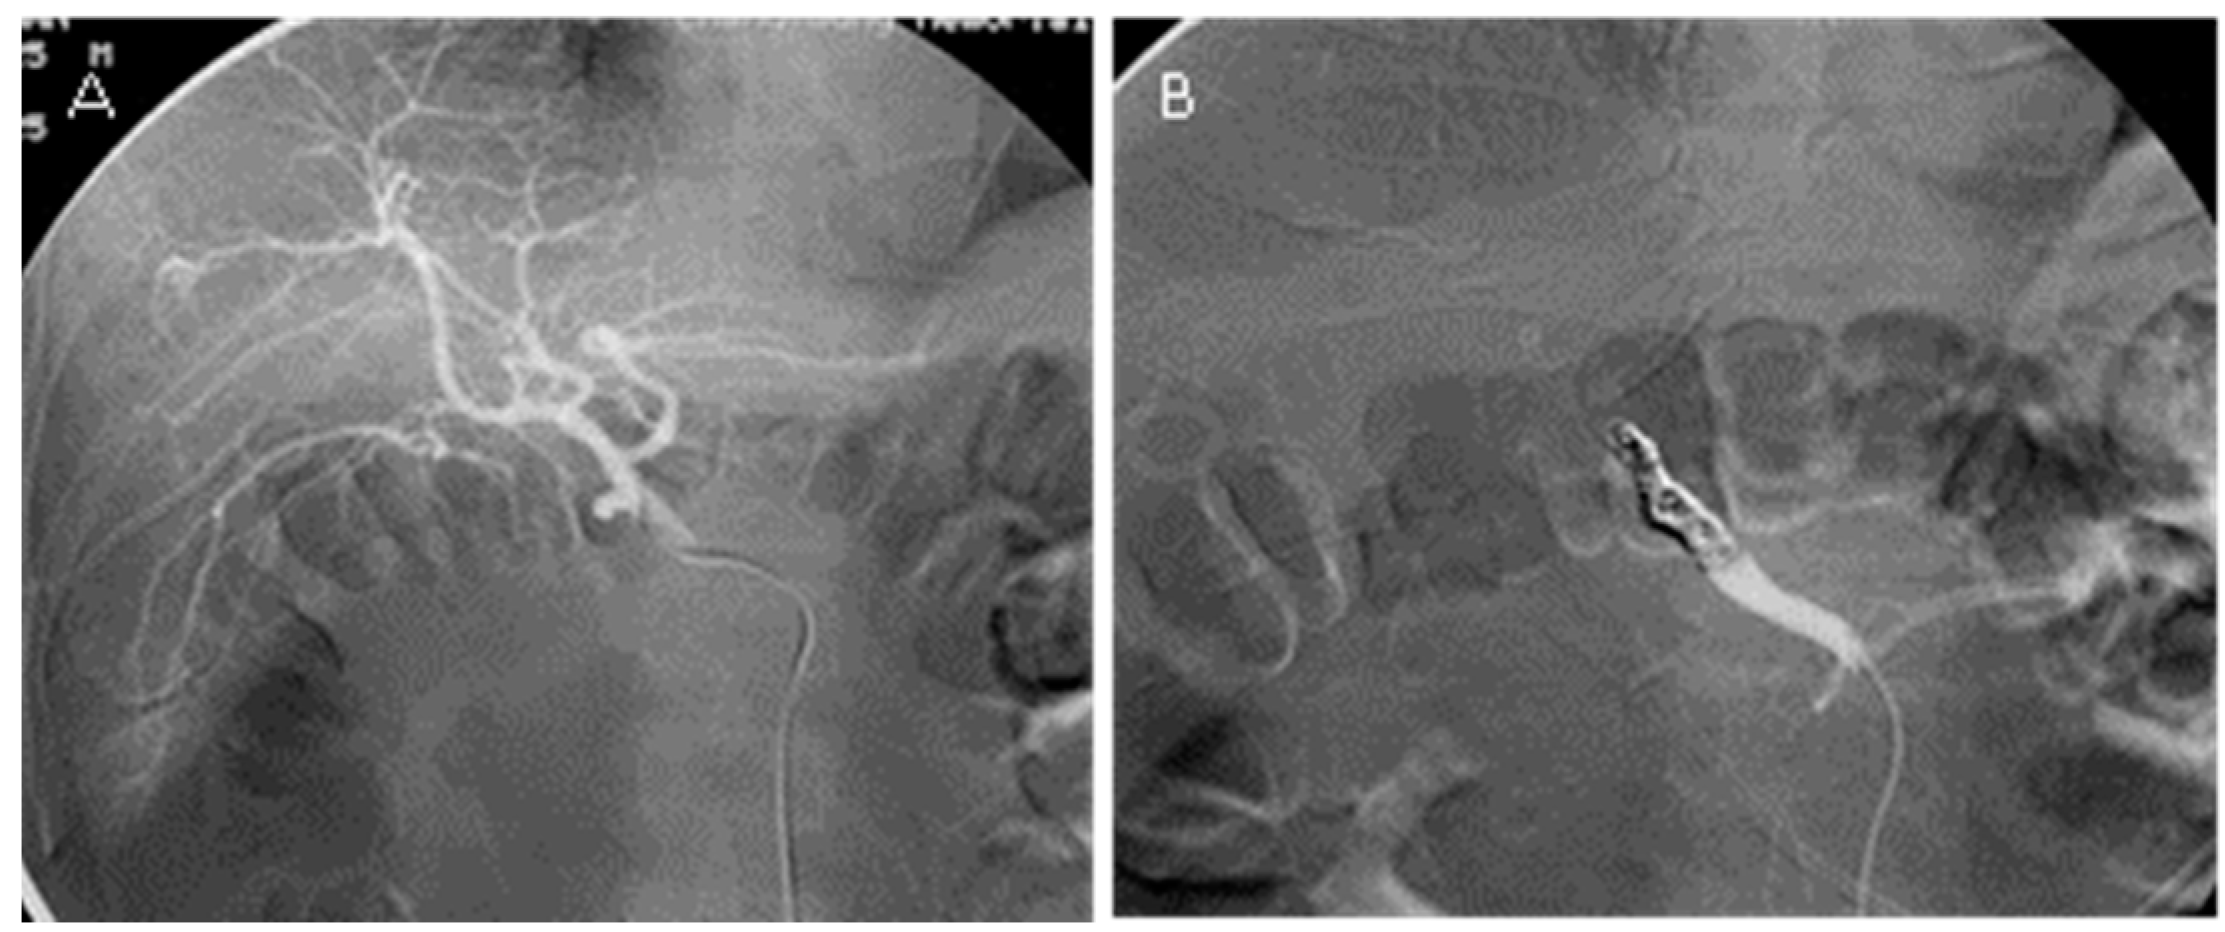

Initial treatment Coil embolization. (A) A TransForm C 4 mm ? 10 mm Coil Embolization And Mri Commonly used embolization coils are either nonferromagnetic or weakly ferromagnetic. Because of the shape of certain. A brain aneurysm coil fills the aneurysm with platinum coils to help form a blood clot, sealing it off and lowering the risk of. Today a significant fraction of intracranial aneurysms are treated endovascularly with detachable coils and stents. In this large, retrospective review. Coil Embolization And Mri.

(A) Proximal and distal right vertebral artery coil embolization. (B Coil Embolization And Mri Commonly used embolization coils are either nonferromagnetic or weakly ferromagnetic. Because of the shape of certain. In this large, retrospective review of patients with implanted ssec undergoing mri, there were no reported adverse events. A brain aneurysm coil fills the aneurysm with platinum coils to help form a blood clot, sealing it off and lowering the risk of. Today a. Coil Embolization And Mri.